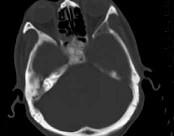

男性,56岁,鼻咽癌放疗后复查,CT扫描如图所示,请选择正确的答案()A.化脓性骨髓炎B.骨结核C.致密性骨炎D.放疗后骨炎E.骨瘤

问题 男性,56岁,鼻咽癌放疗后复查,CT扫描如图所示,请选择正确的答案()

选项 A.化脓性骨髓炎 B.骨结核 C.致密性骨炎 D.放疗后骨炎 E.骨瘤

答案 D